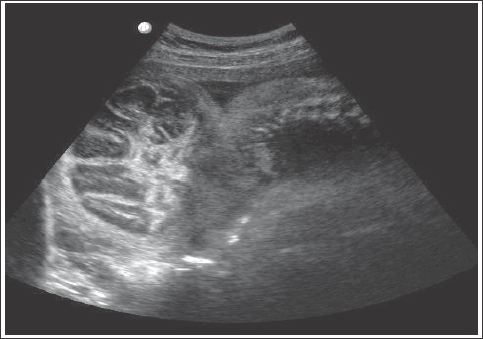

A la paciente se le realiza exámenes de laboratorio obteniéndose datos compatibles con infección urinaria baja, toxo-plasmosis, (IgM positivo IgG negativo) citomegalovirus (IgM positivo IgG positivo) y alfa feto proteína elevada (180 ng/ml). Se realiza un estudio ultrasonográfico, en el cual se observa un feto único vivo de 25 semanas con líquido amniótico normal, placenta alta posterior grado 0. En la cabeza se encuentra una masa encefálica libre rodeada de meninges, con ausencia de calota craneana, muy desplazada hacia la parte posterior; en cara orbitas visibles, nariz y boca normales, base de cráneo aplanado, columna cervical y dorso lumbar normal, tórax y abdomen normales compatible con acrania y cefalocele occipital (fig. 1).

Figura 1. Ecografía obstétrica: masa encefálica libre envuelta por meninges protruye por región occipital.